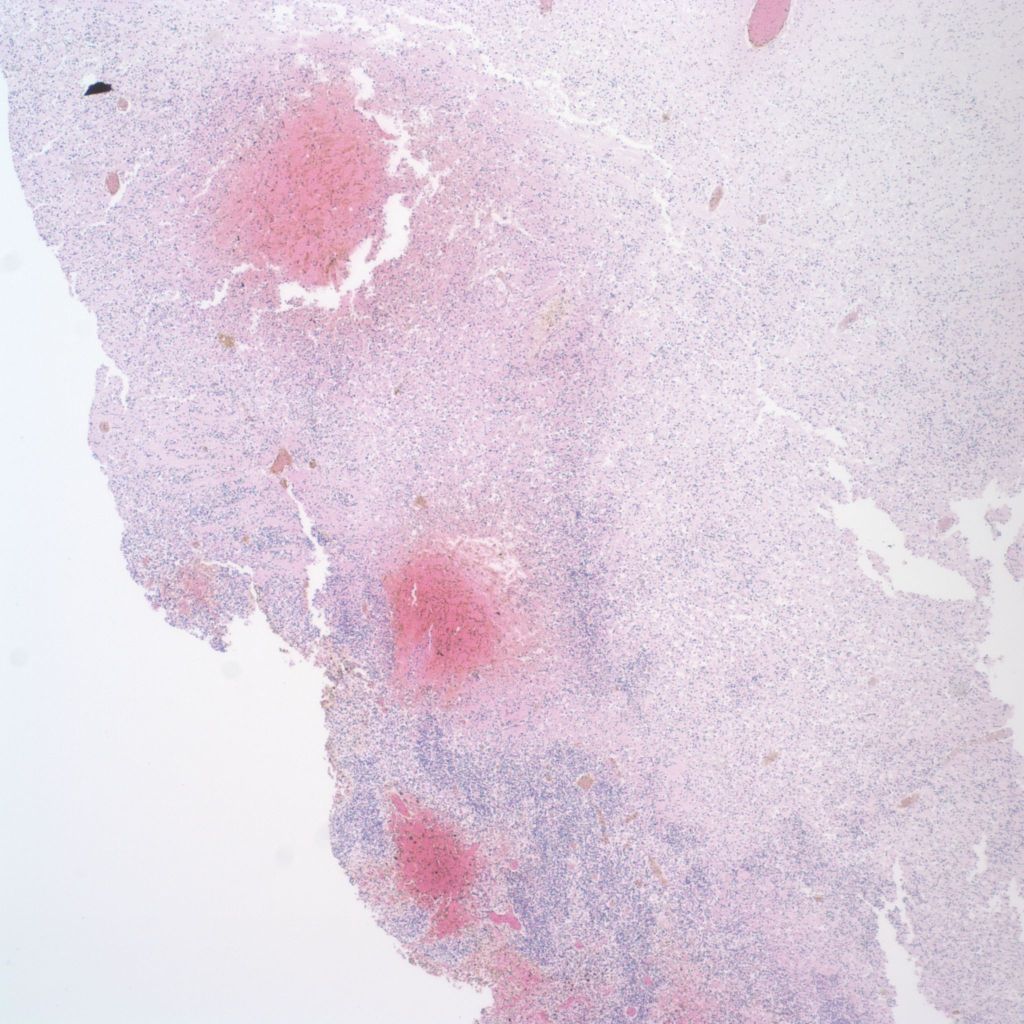

Intraventricular hemorrhage originating in the germinal matrix can often be identified microscopically (19a, b).

Where the hemorrhage extends into surrounding white matter that portion appears necrotic. From the histology, it may not be clear whether the hemorrhage caused the necrosis or the hemorrhage bled into a necrotic area. If the surrounding non-hemorrhagic white matter is necrotic, a reasonable inference is that the hemorrhage passively entered the necrotic area. Not all intraventricular hemorrhages are from the germinal matrix but may occur with other deep brain hemorrhage (Fig 20).